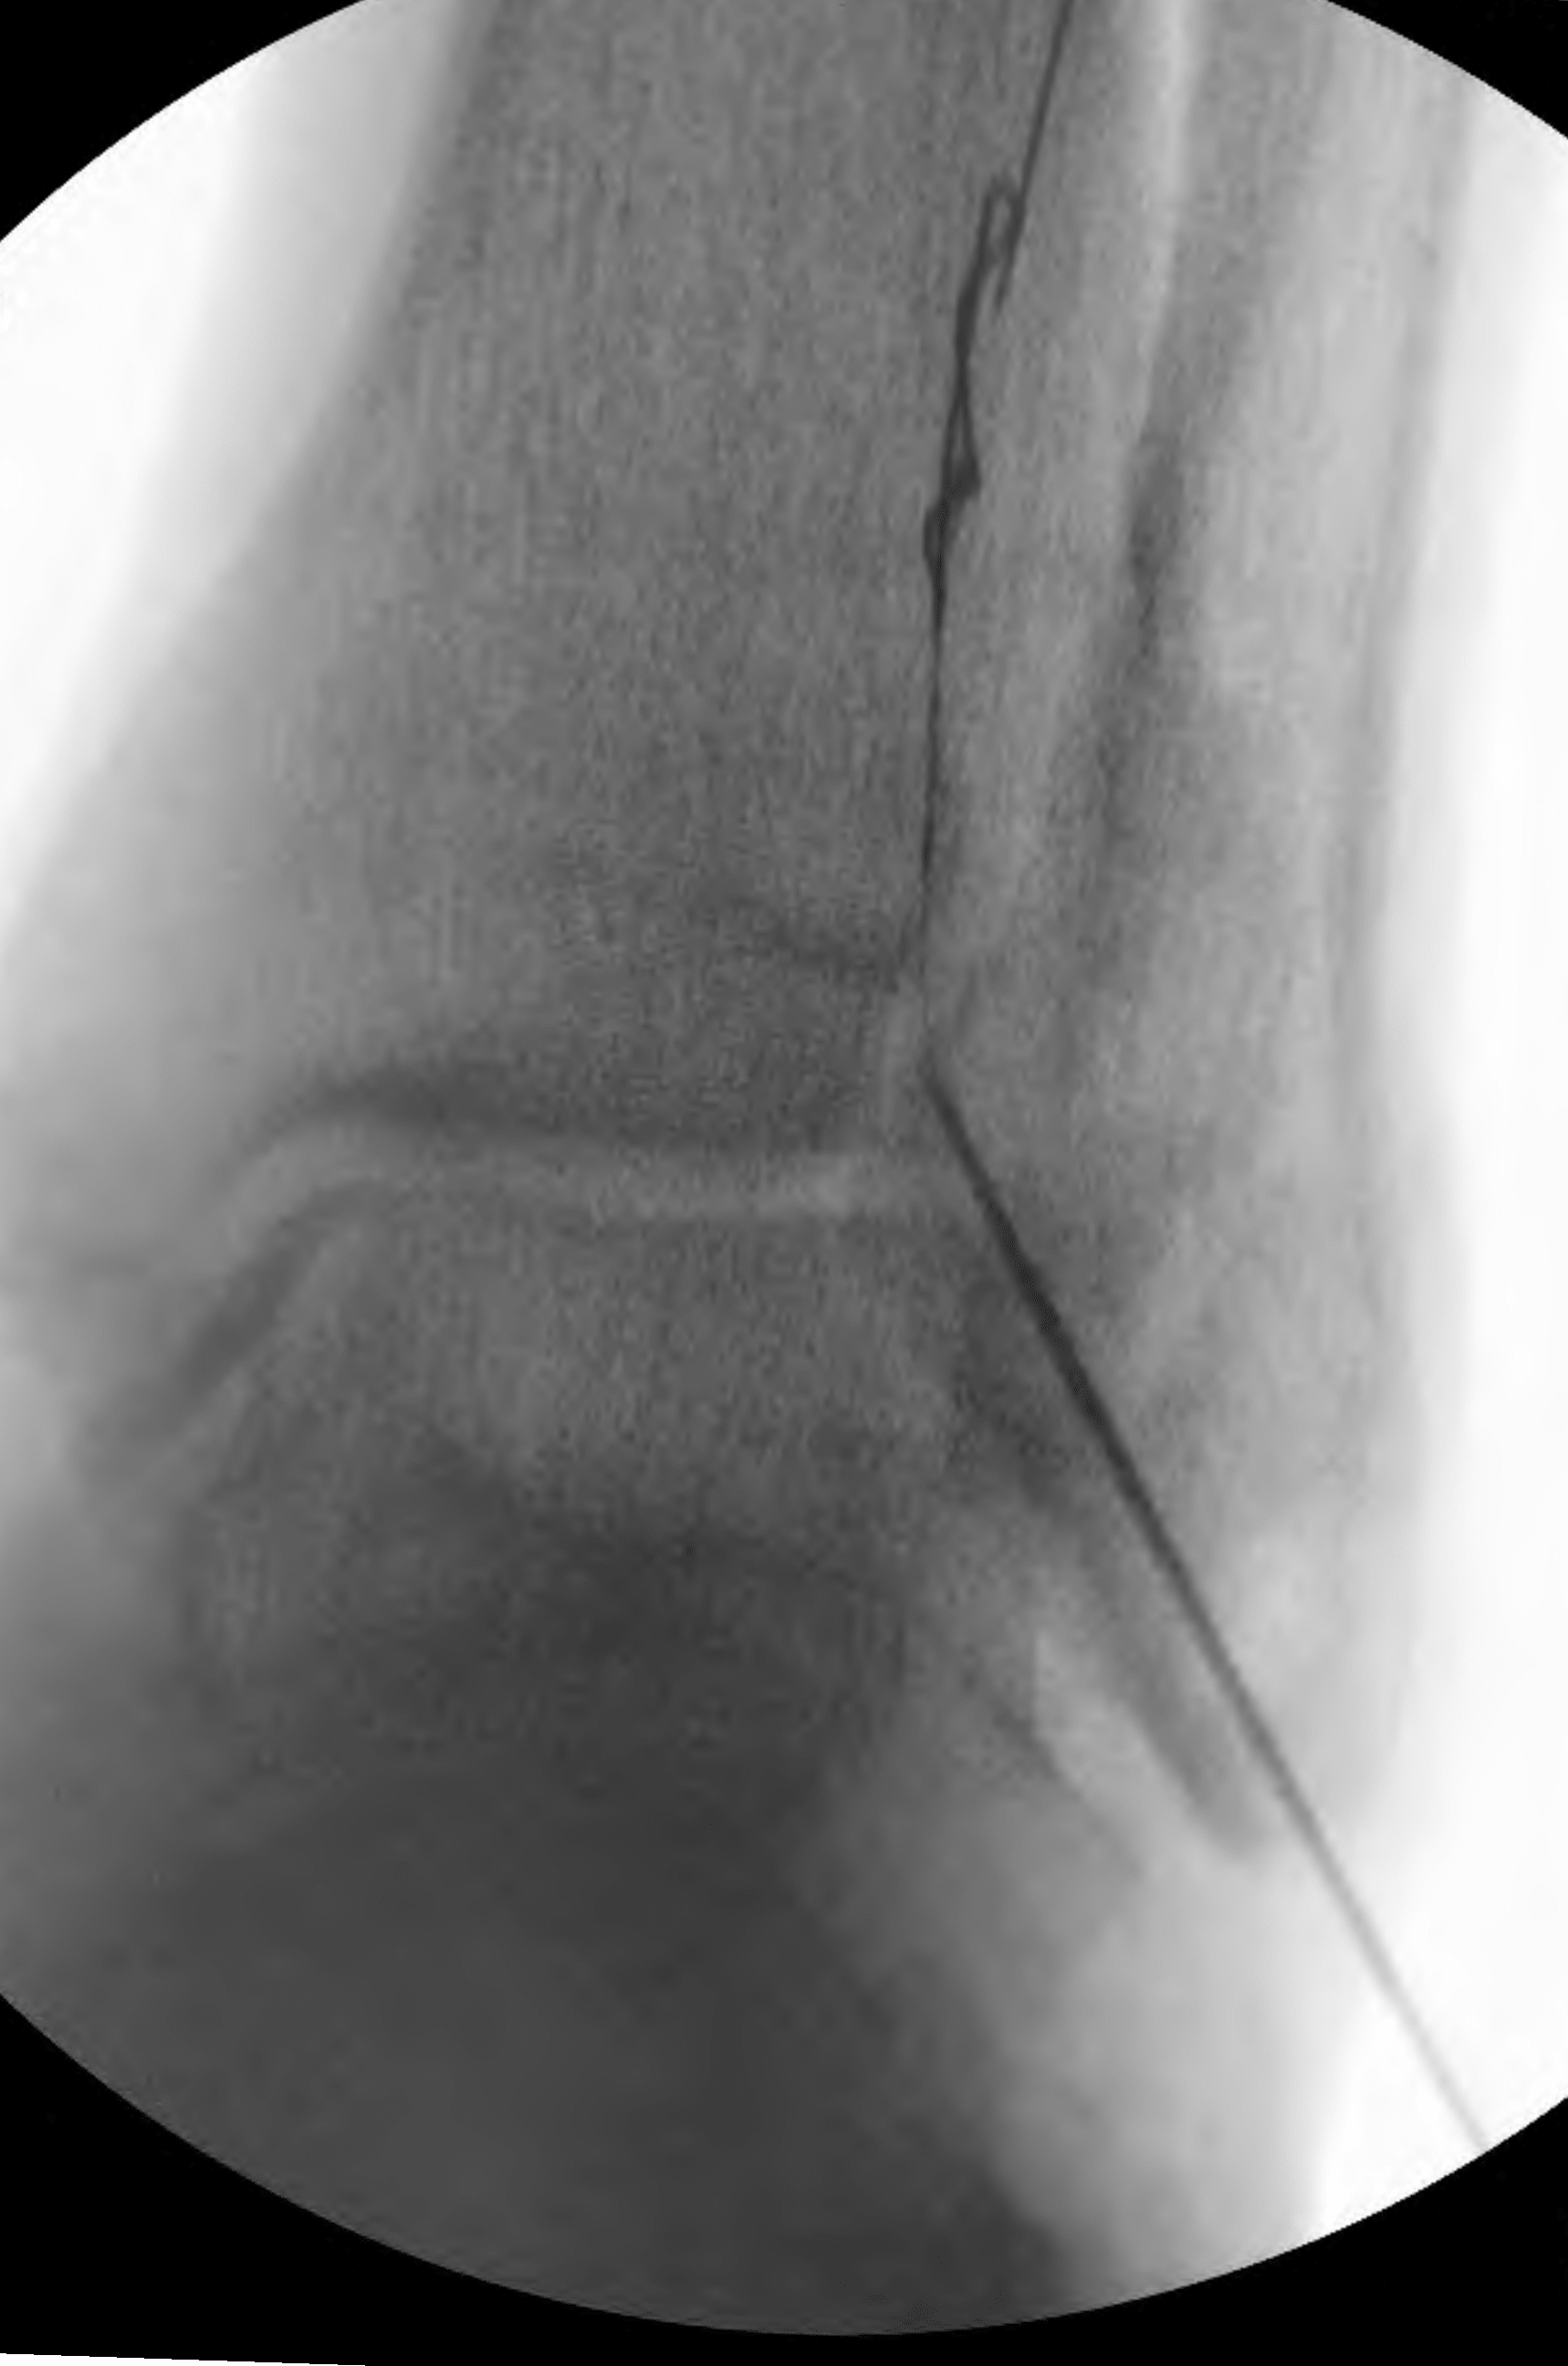

Accessing the occluded segment of an artery has been referred to as the modified Schmidt technique. Real-time ultrasound guidance is useful to accomplish this. After a needle was directed into the occluded anterior tibial artery and visualized within its lumen, a wire was successfully advanced through the occlusion in retrograde fashion into the more proximal anterior tibial artery true lumen. A 2-mm balloon was then advanced “bareback” into the distal occluded segment of the anterior tibial artery and angioplasty was performed (Figure 7). The balloon was withdrawn.